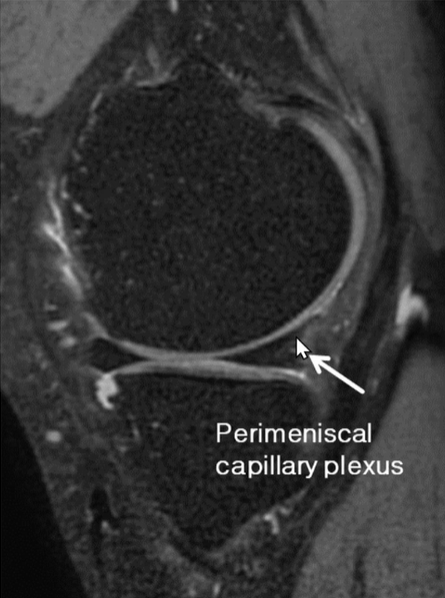

[무릎][MRI] Meniscus & discoid menicus

▶ fibrocartilaginous 구조물로 구성 : Diffuse low signal intensity(검게) on all pulse sequences >...